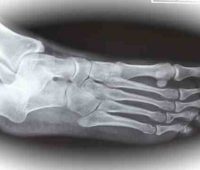

Remedios caseros para las fracturas en el pie

Remedios caseros para las fracturas en el pie Conoce los huesos que se fracturan en un pie Lo mismo que en las manos, los huesos que forman el pie y sus dedos (metatarsianos y calcáneo) pueden fracturarse como consecuencia de una caída, un golpe o un choque con algún objeto pesado. En caso de fractura de los pies hay también dolor, deformación e